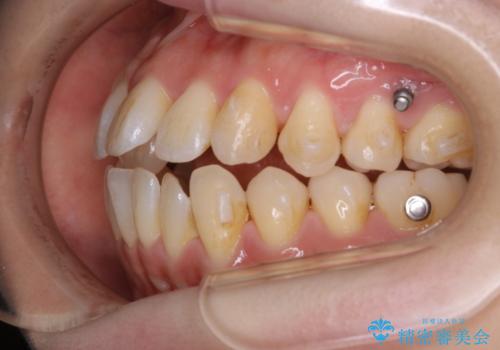

本来は外科ケース:インビザラインで前歯の重度がたつきとオープンバイトの改善

- 前歯のがたつきが気になるとご相談にいらした患者様です。矯正検査の結果、骨格的なズレが大きかったため当初の治療計画では外科矯正をご案内しました。ご本人が手術を望んでおらず、可能な限りの改善を目指すことを目標に治療を開始しました。

元々の骨格的なズレが大きかったため、当初は外科矯正をご提案していました。患者様の強いご希望により、非外科的な処置のみで可及的な改善を目指すことを目標に治療を行いました。以前よりもしっかり噛めるようになり、見た目も劇的に改善したことで大変ご満足いただけました。